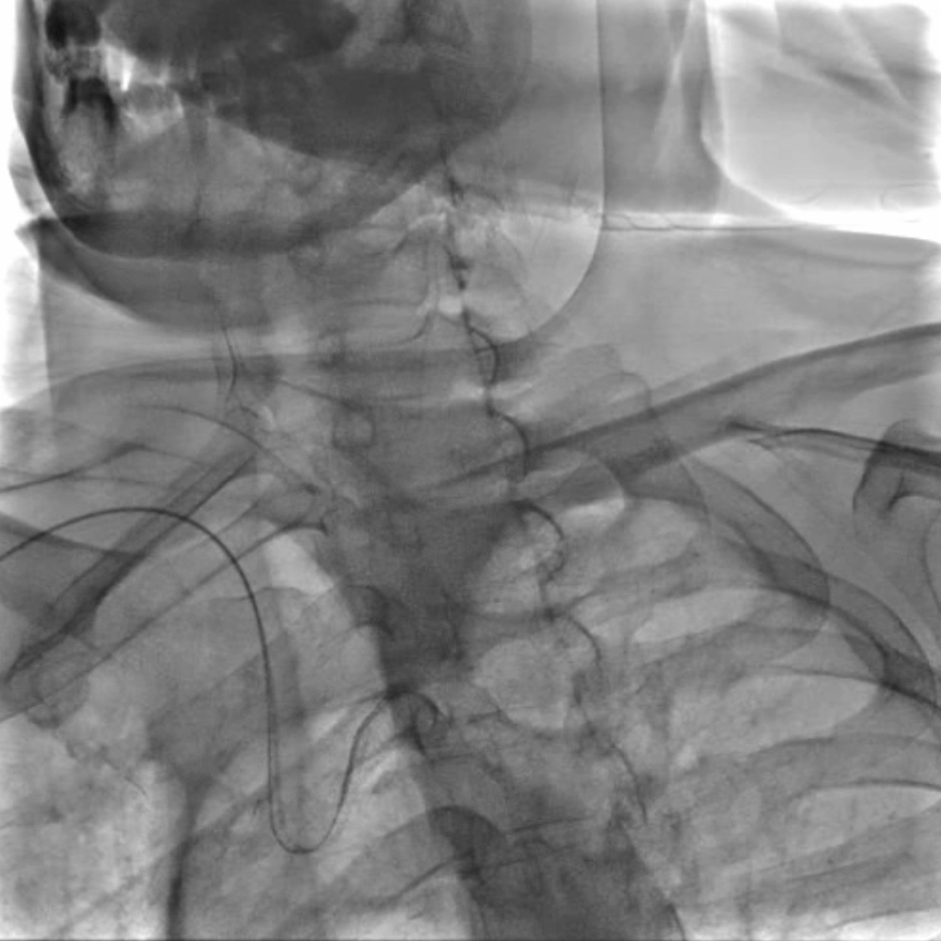

脑保护:Filterwire保护伞的规范使用

选用伞与导丝一体的Filterwire保护伞(on-wire设计),操作要点:导丝尖端柔软,轻松通过狭窄病变;在远端颈内动脉平直段释放保护伞,确保完全贴壁,有效拦截术中脱落的斑块。

预扩张与支架植入:匹配病变特点的器械选择

预扩张:使用5/30mmAviator球囊,扩张前需将患者心率提升至80次/分以上(避免扩张时迷走神经反射导致心率骤降);

支架选择:选用8/40mmPRECISE开环支架,其柔顺性好,适合迂曲的颈动脉解剖结构,定位精准且完全覆盖病变。